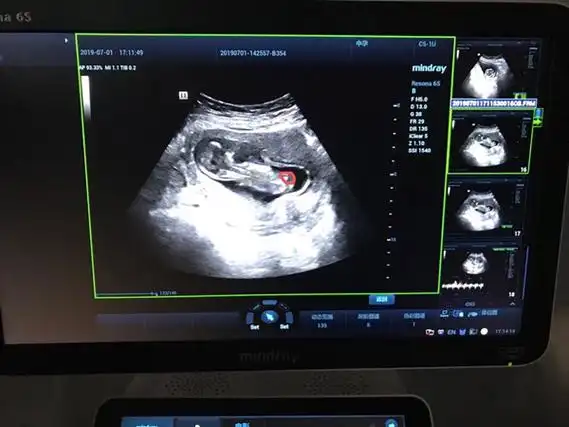

女孩是明显的三条线标志,男孩是明显的小突起亮点,好似男宝的小jj5nt

nt单子男孩有圈圈 男孩性别特征与女孩的不同

刚做完nt 中间那个是脐带嘛,大家可以看出是男宝还是女宝嘛